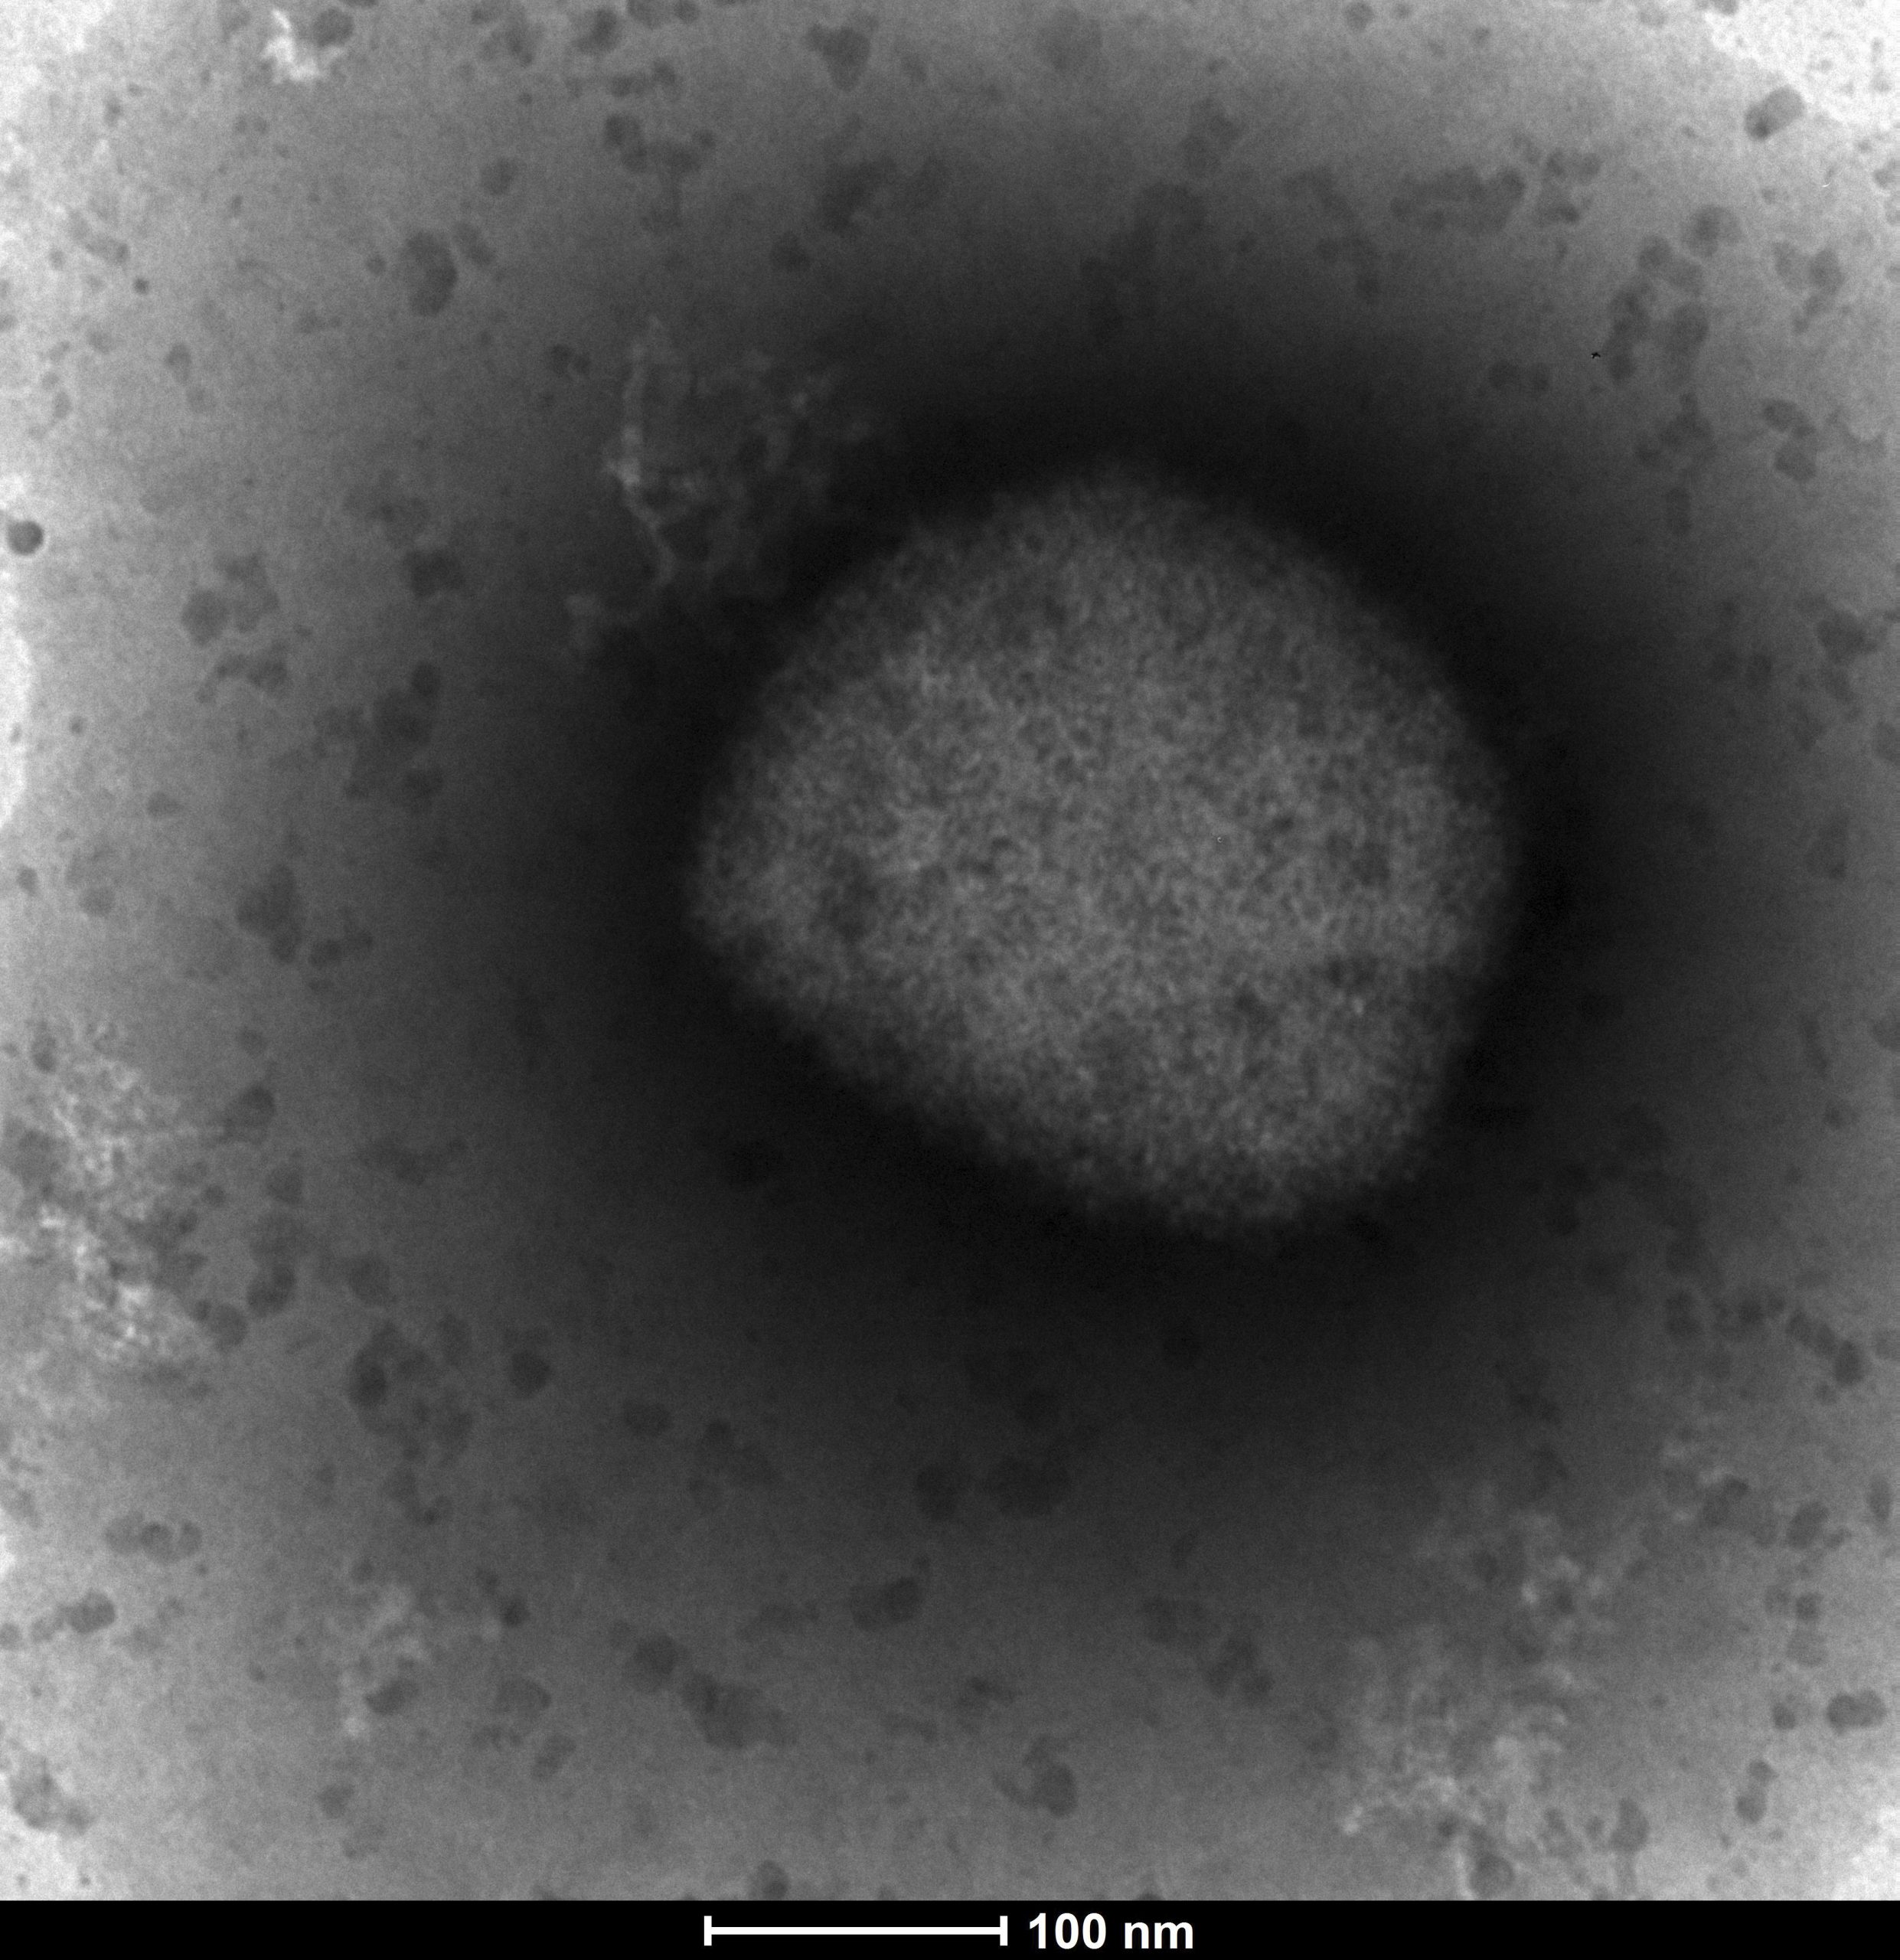

泰国解冻封存超过40年天花疫苗 测试对抗猴痘效力

全球猴痘疫情扩散至少20国,有研究指出,天花疫苗对于猴痘病毒有效。有鉴于此,泰国也宣布计划解冻封存超过40年的减毒天花疫苗,测试确认是否能有效对抗猴痘。